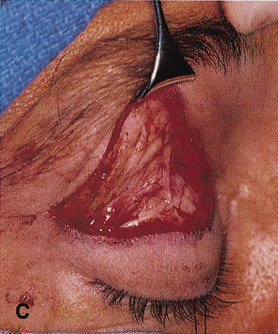

Fig. 11. A. Lateral canthotomy incision is made with straight iris scissors. B. Periosteum is elevated off of the lateral orbital rim. C. Wide undermining allows retraction of the skin incision to permit superior

and inferior osteotomies to be made with the air-driven saw. D. The bony rim has been outfractured. Because of the distensibility of the

skin, it is possible to remove a large bone flap through the small

canthotomy incision. E. The intraconal mass is extracted with the aid of the cryoprobe. F. The bone fragment is positioned for resuturing.

Fig. 11. A. Lateral canthotomy incision is made with straight iris scissors. B. Periosteum is elevated off of the lateral orbital rim. C. Wide undermining allows retraction of the skin incision to permit superior

and inferior osteotomies to be made with the air-driven saw. D. The bony rim has been outfractured. Because of the distensibility of the

skin, it is possible to remove a large bone flap through the small

canthotomy incision. E. The intraconal mass is extracted with the aid of the cryoprobe. F. The bone fragment is positioned for resuturing.

|